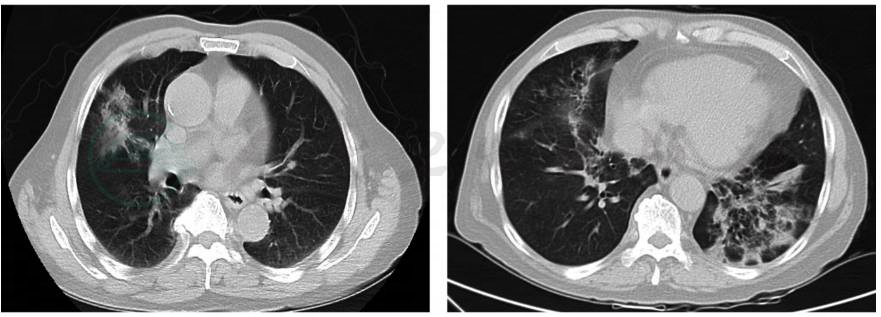

患者体温平,临床症状好转,2017年8月4日复查胸部CT提示病灶较前有所吸收、变淡(图4)。

图4 复查胸部CT平扫:双肺多发阴影,同2017年5月4日比较病灶明显吸收